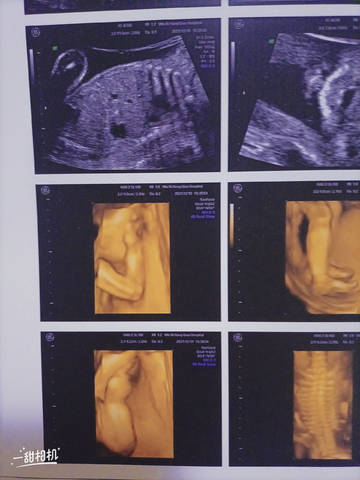

今天做了四维 做了两次都是用手手挡着个脸 医生还说偏小一周 可能预产期推后 可我总是假性宫缩 现在才六个月 感觉好怕 宝妈们你们有木有遇见这种情况

journal_insert_pic_1682616607journal_insert_pic_1682616630